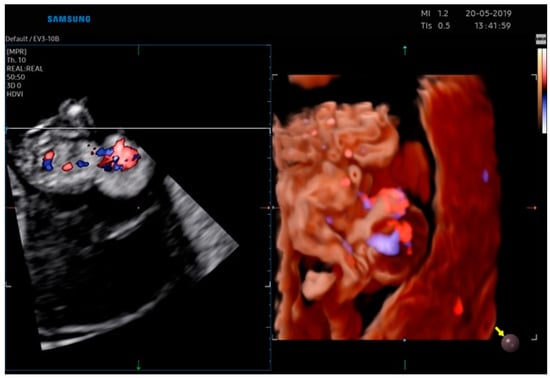

2.1. Case Report 1